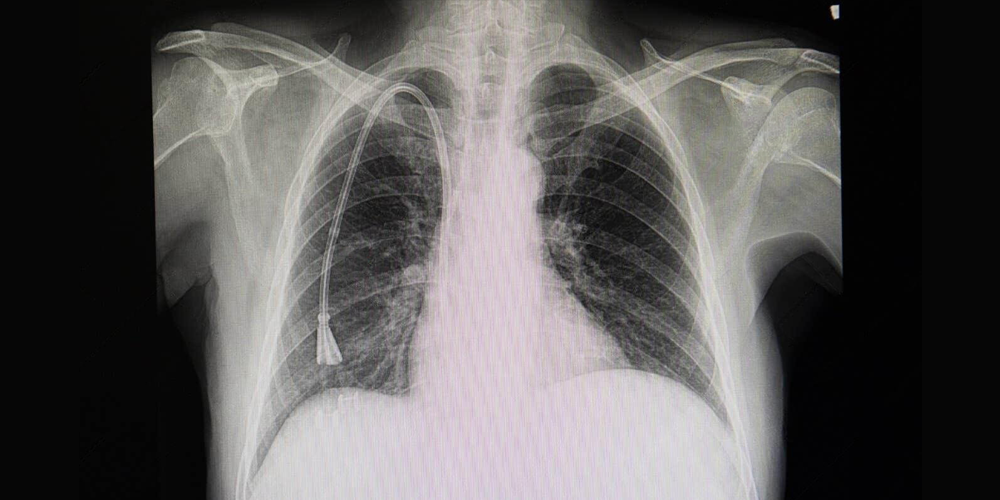

Portanto, um cateter radiopaco é aquele que pode ser visualizado em exames de raio-X, garantindo controle visual do trajeto e da posição da ponta do dispositivo.

Em procedimentos invasivos, o posicionamento por imagem é um dos principais fatores associados à segurança em cateterização. A inserção de um cateter sem confirmação visual adequada pode resultar em mau posicionamento, necessidade de reposicionamento ou até complicações clínicas.

O Cateter Venoso Central é amplamente utilizado para administração de medicamentos, soluções parenterais, nutrição e monitorização hemodinâmica. A presença de radiopacidade permite confirmar o posicionamento adequado da ponta do dispositivo por meio de exame radiográfico.

Já os Cateteres para Hemodiálise auxiliam no tratamento de hemodiálise em pacientes portadores de insuficiência renal crônica ou aguda. Neste contexto, estes dispositivos exigem posicionamento preciso para garantir fluxo sanguíneo adequado.

Nesse cenário, o cateter radiopaco facilita a confirmação do local de implantação, permitindo visualização clara em raio-X. Consequentemente, a radiopacidade auxilia na validação do posicionamento e no acompanhamento do dispositivo ao longo do uso clínico.

O Cateter Central de Inserção Periférica, também conhecido como cateter PICC, é introduzido por acesso periférico e avançado até a circulação central. Como o trajeto percorre estruturas vasculares extensas, a visibilidade radiográfica torna-se essencial.

O termo Cateter radiopaco refere-se a um dispositivo capaz de ser visualizado em exames de imagem, graças à incorporação de materiais que aumentam sua radiodensidade. Essa característica permite confirmação do posicionamento, monitoramento do trajeto e maior segurança em procedimentos invasivos.

Além disso, a radiopacidade contribui para controle clínico mais preciso, especialmente em contextos que exigem punção assistida e fluoroscopia.